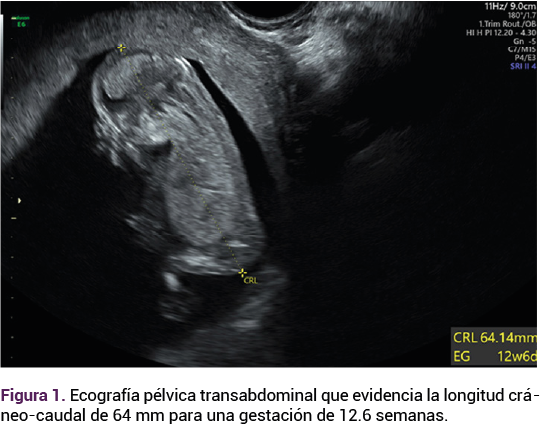

El reporte anatomopatológico y microscópico identificó mola hidatiforme parcial coexistente con un feto (Figuras 3, 4 y 5). Durante el seguimiento, la paciente no tuvo complicaciones aparentes y mostró un descenso significativo en las concentraciones de la gonadotropina coriónica humana.

<strong>Figura 3</strong>

Figura 3.